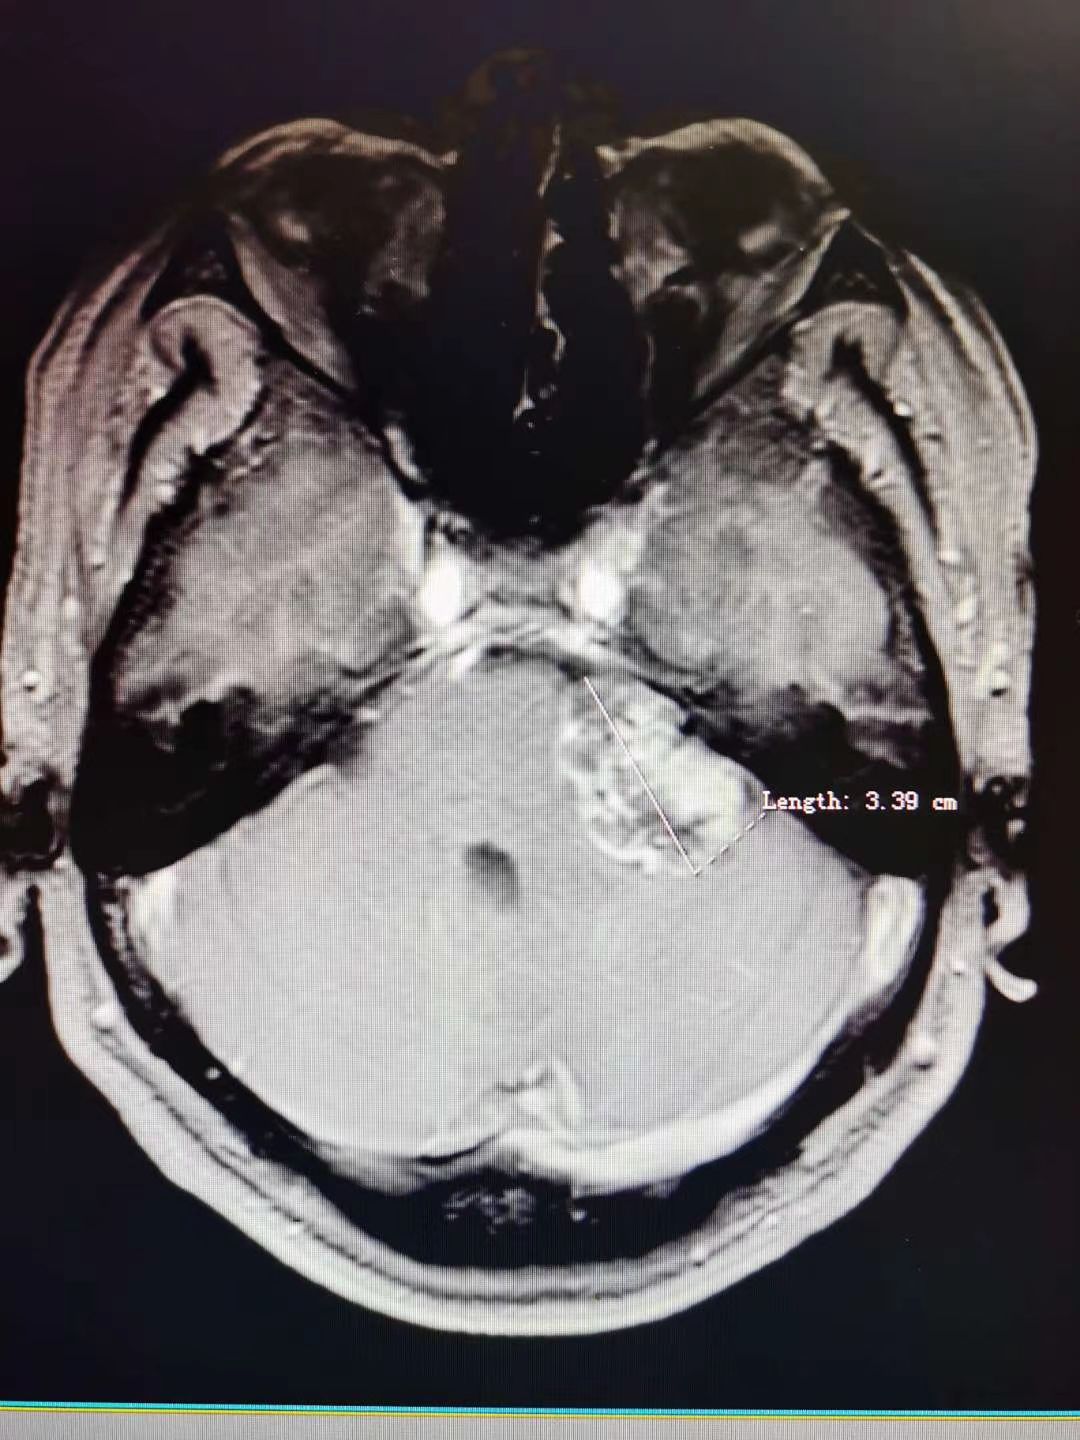

听神经瘤1例

肿瘤全切,术后面神经功能保留完好